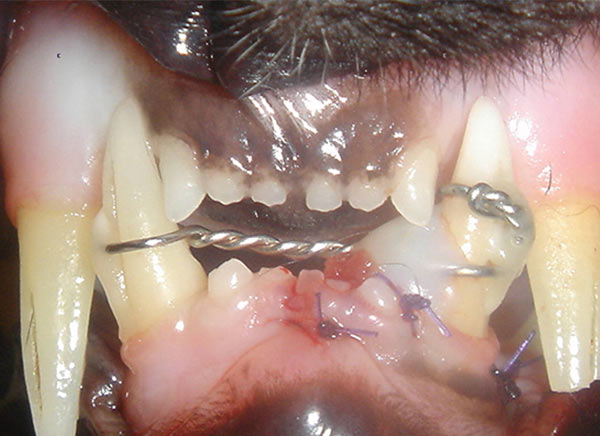

Accidents happen. As a dental specialty practice, we see the full spectrum of oral and facial injuries. Jaw fractures can occur due to blunt force trauma, rough play with other animals, dental disease or bone disease. Injuries to the mandible or maxilla can have consequences for how your pet’s teeth and jaws can be used to chew and play for years to come.